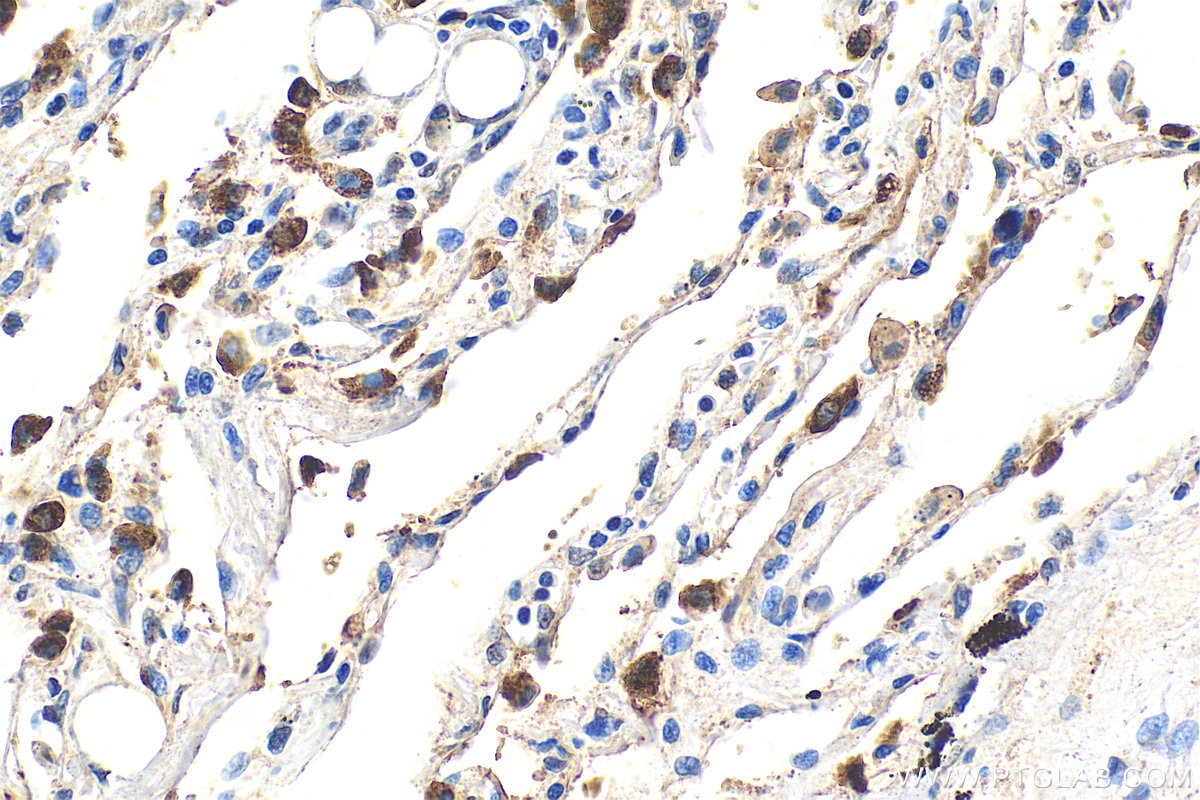

| Positive IHC detected in | human lung tissue Note: suggested antigen retrieval with TE buffer pH 9.0; (*) Alternatively, antigen retrieval may be performed with citrate buffer pH 6.0  |

| Immunohistochemistry (IHC) | IHC : 1:500-1:2000 |

10774-1-AP targets SFTPC in WB, IHC, IF-P, ELISA applications and shows reactivity with human, mouse, rat samples.